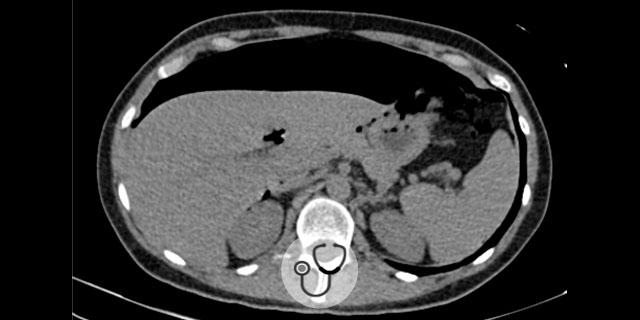

Paciente 50 anos, sexo feminino, dá entrada na emergência relatando dor abdominal no quadrante superior e inferior esquerdo.

Familiares negaram febre, espirro e coriza. História patológica pregressa de hipertensão arterial sistêmica e outras condições.